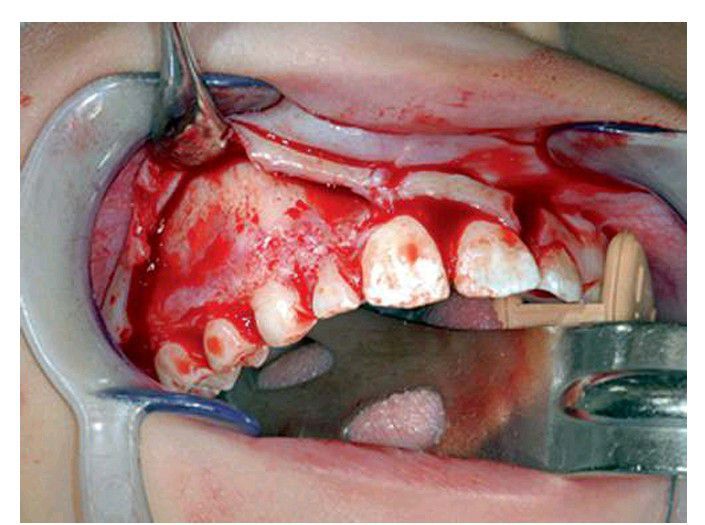

A periosteal elevator is used to retract the mucoperiosteal flap. The elevator is placed perpendicular to the bone and held in place by pressing firmly against the bone, not by pushing it apically against soft tissue. Notice the vertical releasing incision located at the distal line angle of tooth #9.